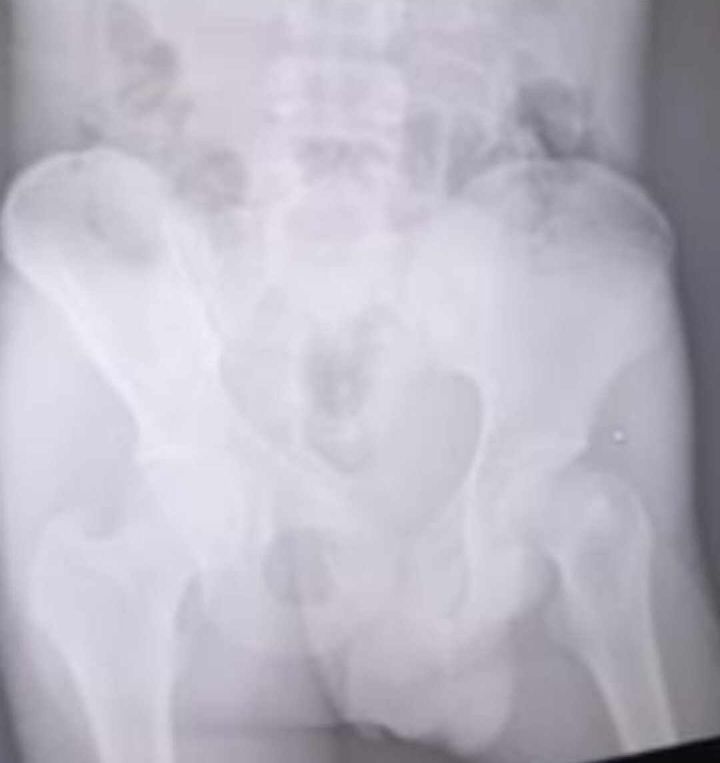

Redacción / La Voz de Michoacán Morelia, Michoacán. Un menor de edad resultó lesionado tras el choque de dos vehículos en el Acueducto de Morelia, percance que ocurrió durante la madrugada del pasado sábado 14 de septiembre. De acuerdo con la información compartida por los testigos, el accidente ocurrió aproximadamente a las 22:00 horas, cuando una camioneta Nissan X-Trail color negro se impactó contra otro vehículo a la altura de la XXI Zona Militar, en la colonia Vasco de Quiroga. Derivado del impacto, la camioneta se estrelló contra uno de los arcos del Acueducto y atropelló al menor de edad, quien se encontraba subiendo las escaleras que están debajo del Acueducto. Familiares del menor de edad han pedido ayuda para difundir las imágenes y poder dar con el paradero de los dueños de los vehículos. Detallaron que las autoridades municipales no pusieron a disposición los vehículos y que, hasta el momento, no hay personas detenidas. Así mismo, han dado a conocer que el menor de edad se encuentra en el Hospital Infantil de Morelia con fractura de cadera y fémur. “Exigimos respuestas y que se hagan responsables de los daños”, agregó una de sus familiares.